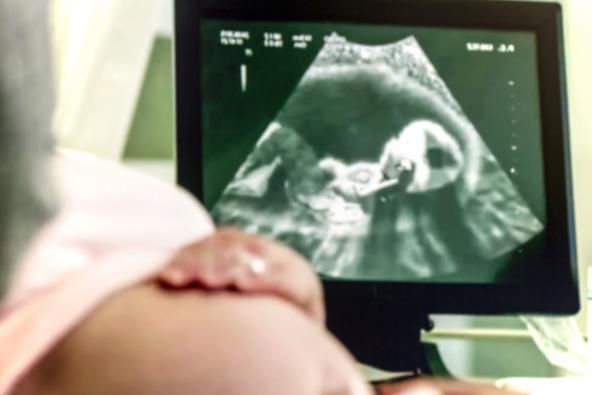

Analiza rutinskih prenatalnih ultrazvučnih snimaka napravljenih tokom drugog tromesečja trudnoće pokazala je da 30% fetusa kod kojih je kasnije dijagnostikovan autizam ima karakteristične abnormalnosti u strukturi srca, bubrega i mozga.

Učestalost takvih fetalnih anomalija kod dece sa ASD (poremećaj iz spektra autizma) je tri puta veća nego među njihovom neurotipičnom braćom i sestrama i tri puta veća nego među neurotipičnom decom bez ASD.

Ovi znaci, koji se mogu videti tokom rutinskog ultrazvuka u 20. nedelji, omogućiće lekarima da proaktivno procene šanse da nerođena beba razvije ASD, primećuju istraživači.